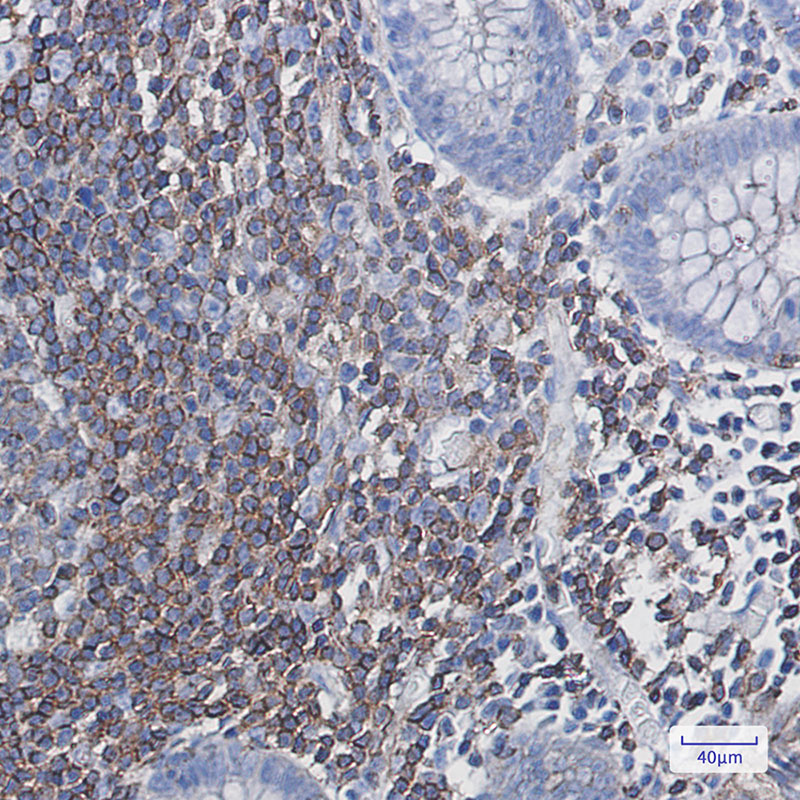

PHD3 monoclonal antibody

Product Name :PHD3 monoclonal antibody

Applications :WB,IHC-P,IP

Application_all :WB: 1/500-1/1000 IHC: 1/50-1/100 IP: 1/20

Western blot analysis of PHD3 in Hela lysates using PHD3 antibody.

Western blot analysis of PHD3 in rat lung and mouse lung lysates using PHD3 antibody.